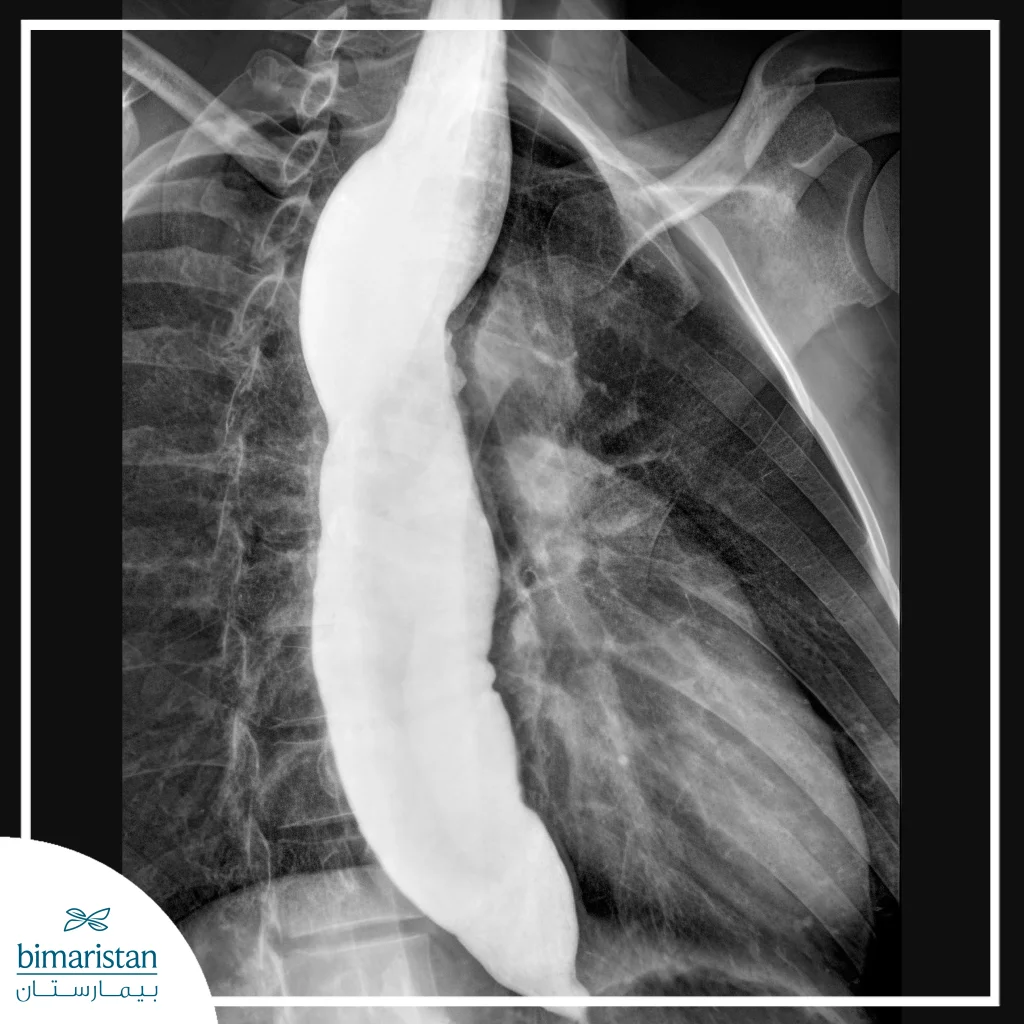

X-rays and barium

Esophageal balloon dilation is often preceded by imaging tests, such as barium X-rays, to assess the severity of the esophageal stricture. The patient swallows liquid barium, a contrast agent that appears clearly on the X-ray, allowing the shape and location of the esophagus and any stenosis to be monitored. This test is useful for determining the length and severity of the stricture, as well as detecting any abnormalities or disturbances in the movement of the esophagus.